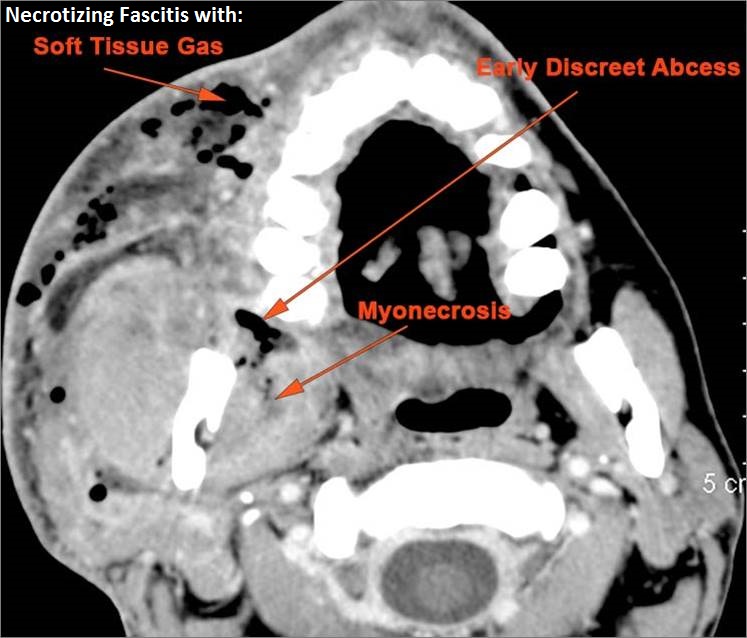

There is significant secondary airway encroachment present.

There is evidence of thrombus, thrombophlebitis or other occlusive or inflammatory process of the jugular vein or smaller venous tributaries.

Other significant abnormal findings are present.